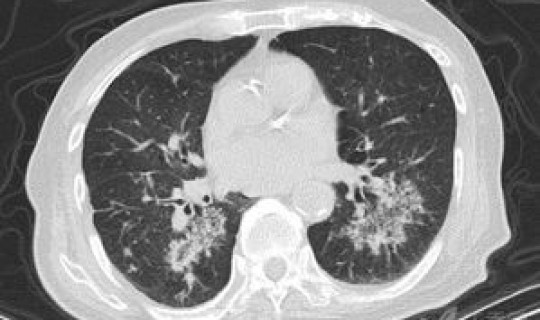

患者范某某,42岁男性 ,德州市庆云县人 。1月21日,自驾车从庆云县到首都国际机场,之后由芝加哥机场转机到奥兰多探亲。3月7日由美国奥兰多经纽约转机于3月8日乘坐CA982航班到达首都国际机场 ,体温检测无异常。3月9日凌晨乘坐庆云县安排的专车返回当地集中隔离点进行集中隔离 。3月11日病毒核酸检测结果阳性,随即转送至庆云县定点医院进行隔离治疗,入院后进行血液检查 、CT肺部影像检查 ,检查无异常,经专家组评估确定为无症状感染者。市疾控中心将相关情况及时 *** 通报并函告北京市疾控中心、北京市出入境检验检疫部门。市、县两级疾控中心会同海关 、公安等部门加紧开展密切接触者排查追踪等工作,截至发布前已追踪到密切接触者10人 ,全部实行集中隔离医学观察 。3月15日,患者出现咳嗽、咳痰症状,无发热以及其它不适,复查胸部CT显示左肺单发磨玻璃斑片影。3月16日 ,经专家组评估确诊,当天下午转送至山东省定点医院进行隔离治疗。